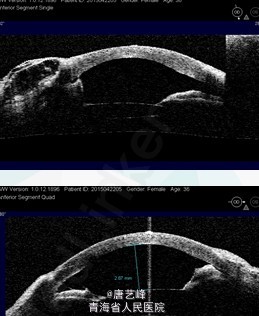

眼部检查: 视力:VOD:0.1 ,VOS:光感,IOP:OD 8mmHg,OS 18mmHg,右眼角膜轻水肿,中央前房深度 1.1mm,周边周边消失,虹膜部分萎缩,瞳孔3×3mm,晶体混浊,眼底窥不入。左眼无充血,角膜中央白色雾状混浊,约直径4mm,中央前房深度消失、周边周边消失,瞳孔大小正常,晶体前白色渗出膜,眼底窥不入。

1.右眼抗青光眼术后浅前房 2.左眼抗青光眼术后无前房 3.双眼并发性白内障 处理:右眼白内障超声乳化抽吸术+人工晶体一期置入术+前段玻璃体切除术

右眼术后半个月视力0.3,眼压13mmHg,结膜充血,滤过泡隆起,角膜雾状水肿,中央前房深,前房注气尚未吸收,瞳孔约4×4mm,人晶在位。左眼无充血,角膜中央白色雾状混浊,约直径4mm,前房消失,瞳孔大小正常,晶体前白色渗出膜,眼底窥不入。 讨论:1)年轻慢闭易发生术后浅前房原因:眼轴短、前房浅、晶状体厚、睫状突位置靠前、脉络膜增厚、其他后房压力增大的因素(本例B超报告右眼眼球壁增厚) 2)抗青术后浅前房处理:保守治疗:全身及局部抗炎、脱水、散瞳 手术治疗:前房形成、结膜瓣修复睫状体-脉络膜脱离引流、扁平部穿刺抽吸玻璃体积液、前段玻璃体切除、白内障超声乳化抽吸术